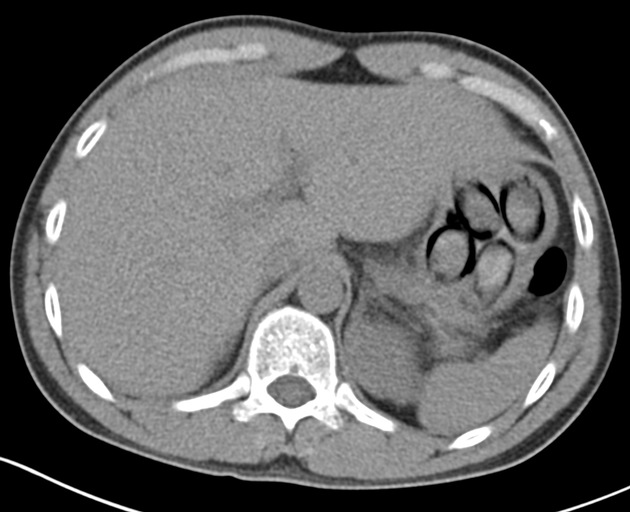

"Die Röntgenaufnahme in einem nahegelegenen Krankenhaus bestätigte letztendlich den Verdacht meiner Kolleginnen und Kollegen, denn im Magen des Mannes waren mehrere Drogenpäckchen klar zu erkennen. Insgesamt schied der Mann dann unter Überwachung sieben sogenannte Bodypacks mit insgesamt mehr als 100 Gramm Kokain aus", so Jens Ahland, Pressesprecher des Hauptzollamts Köln.